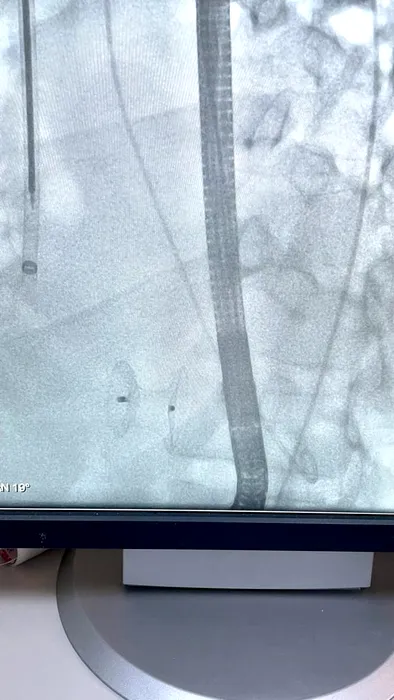

EXCLUSIV. Pacient cu infarct devastator salvat printr-o intervenție de excepție, la Institutul Inimii din Capitală, de echipa medicului Dan Deleanu. Ce presupune intervenția (FOTO)